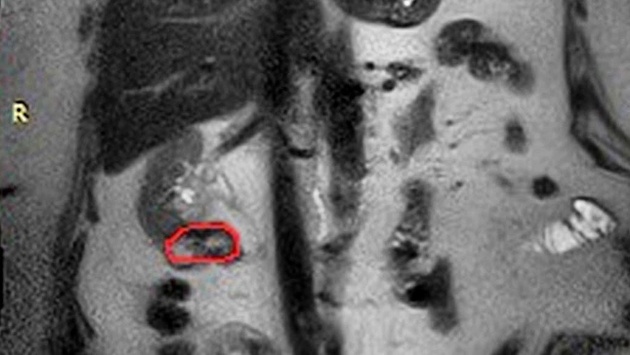

Ранее у 73-летней нижегородки полностью удалили левую почку и провели частичную резекцию правой. Некоторое время спустя, когда женщина проходила контрольное обследование, врачи выявили у нее рецидив опухоли в сохраненной почке.

Врачи НОКБ им. Семашко провели операцию, удалив опухоль. Правую почку удалось сохранить. Уточняется, что кровообращение в сосудах пациентки останавливали на семь минут.